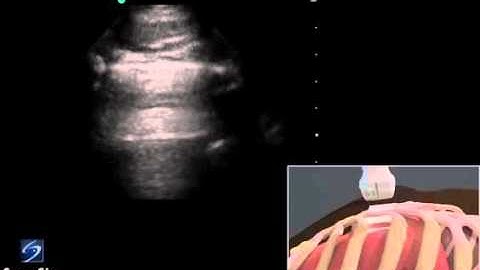

How To: Lung Sliding Detection with Linear Transducer 3D Video